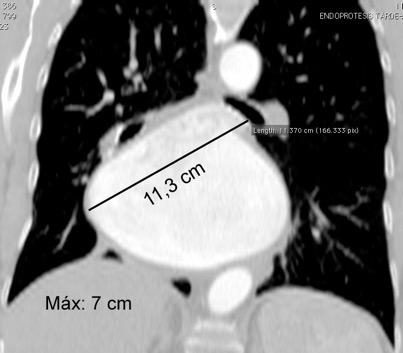

Diámetro borde cardiaco derechopared inferior del bronquio principal izquierdo debe ser en el normal < 7cm

Higgins CB et al. Left atrial dimension on the frontal thoracic radiograph: a method for assessing left atrial enlargement. AJR 1978